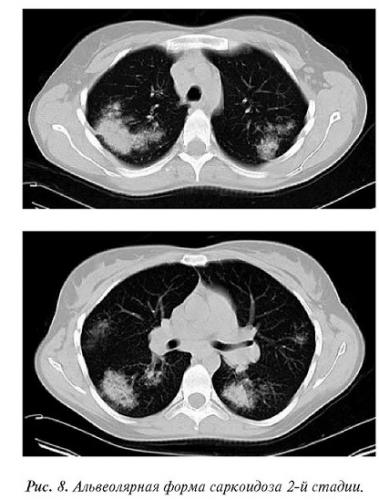

- Дифференциальная диагностика с другими заболеваниями (рак легких, туберкулез, пневмокониозы, саркоидоз).

- Перилимфатический очаг – часто наблюдается в бронхах, сосудах, в междольковых перегородках и листках плевры. В таком случае видны неровные контуры анатомических структур, при этом перегородочки и стенки бронхов несколько утолщены, как и стенки сосудов. Подобные патологические изменения часто встречаются при туберкулёзе, силикозе, саркоидозе и карциноматозе. При этих патологиях очаги небольшие и не превышают 2-5 мм. Состоят такие очаги из гранулем или метастатических узелочков, они наблюдаются вдоль лимфатических узелков в ткани лёгких и плевре.